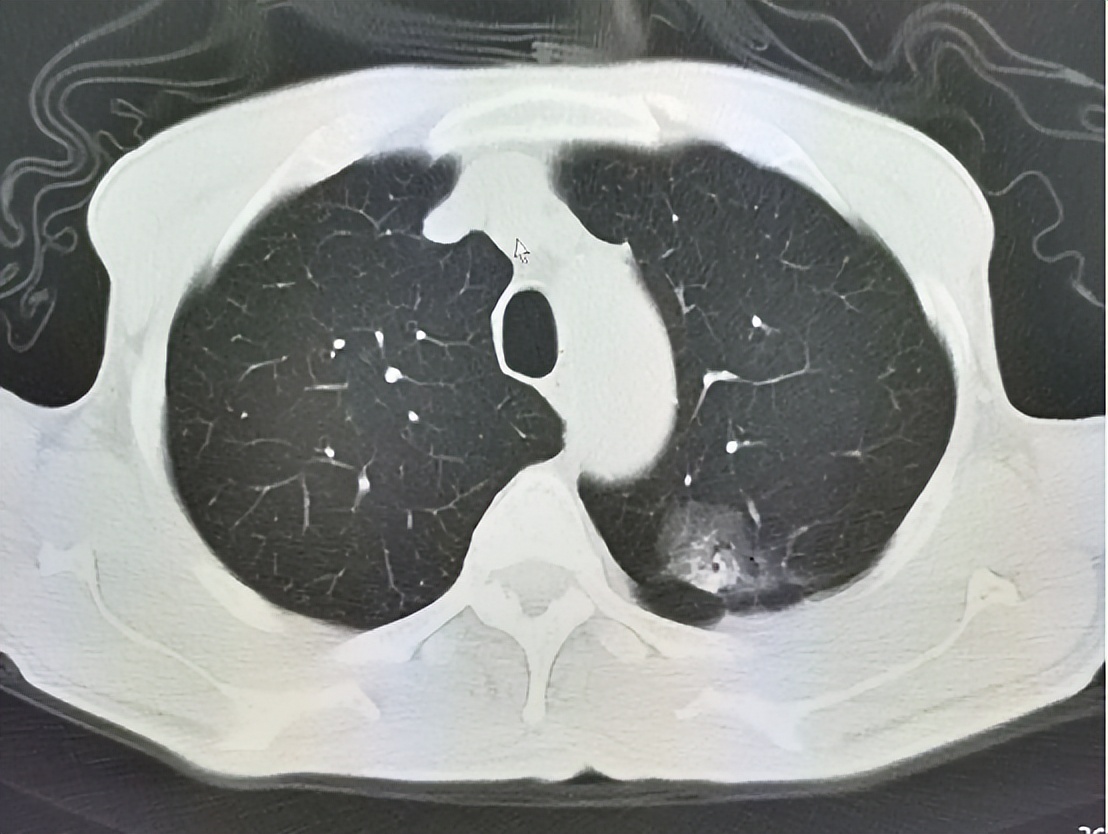

GGN指的是胸部CT影像上表现为密度轻度增高的云雾状淡薄影,样子像磨砂玻璃,所以叫磨玻璃结节。GGN根据有无实性成分分为纯GGN和混和型GGN。如果病灶内只用磨玻璃成分,不含有实性成分,称为纯磨玻璃结节;如果既有磨玻璃成分,又含有实性成分,则称为混和型磨玻璃结节。GGN中的磨玻璃成分对应的是病理上的鳞屑样生长方式,影像学上表现为磨玻璃样影,指异常增生的上皮细胞或分化良好肿瘤细胞以鳞屑样生长或贴壁样生长,表现为增生的细胞沿现有的结构和肺泡壁生长而不侵犯基质、胸膜或血管,保持完整的肺泡结构,基底膜仅有轻度反应。它打破了恶性肺部肿瘤生长或倍增的“两年定律”,不遵守PET检查SUV值增高的规律,表现为非常明显的惰性生长的特点,直径倍增时间可长达3-5年。

目前认为,GGN是遵循不典型增生(AAH)→原位癌(AIS)→微浸润腺癌(MIA)→浸润性腺癌的直线式发展模式的,从影像学角度来看,GGN是从纯磨玻璃结节逐渐发展为部分实性或实性结节,实性成分含量越高,其恶性程度也越显著。各病理阶段的磨玻璃结节预后情况分别如下: